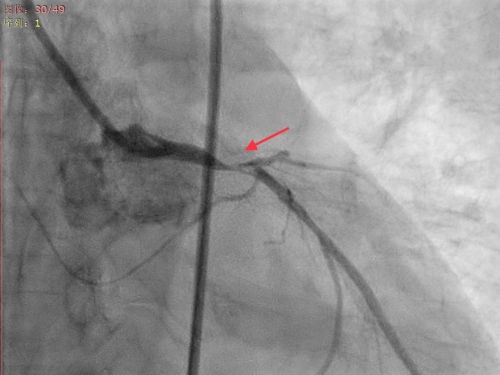

谁知,王女士刚进手术室大门便突发意识丧失,心电监护提示反复室颤。医护人员立即展开抢救,先后为她进行电除颤10余次。因患者病情来势凶猛,随时有生命危险,心内三科主任潘宏伟主任医师与张宇副主任医师、胡勇军副主任医师等立即为她施行急诊床旁主动脉球囊反搏(IABP)植入术及呼吸机辅助呼吸。随后的急诊冠脉造影证实为——冠脉左主干99%狭窄并伴有血栓,前降支完全闭塞。医生立即为她进行经皮冠状动脉介入治疗(PCI),在病变血管内放置支架,迅速打通王女士闭塞的血管。